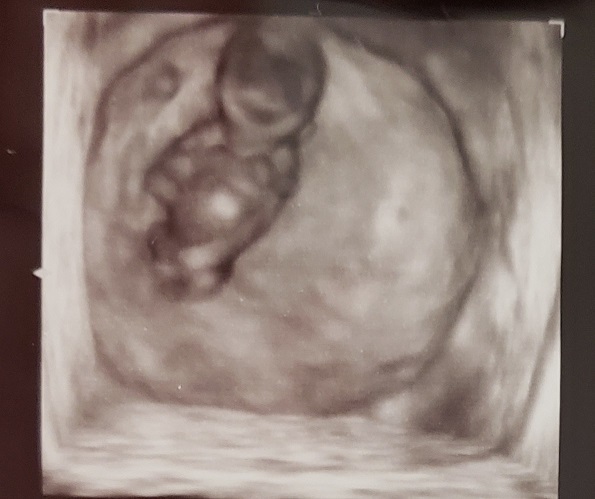

10週4日(10w4d・性別不明)|yK1123 さん(30歳)

エコー写真撮影時のエピソード:

ずーっと胃が気持ち悪くて、食べても食べなくても気持ち悪くて、とてもしんどかったです。

体の節々もだるかったです。

吐くことはなかったので、その時々で食べたいものを食べていました。

このエコーは初めての3D!羊水の中でぷかぷかしている姿が見れて、感動しました。